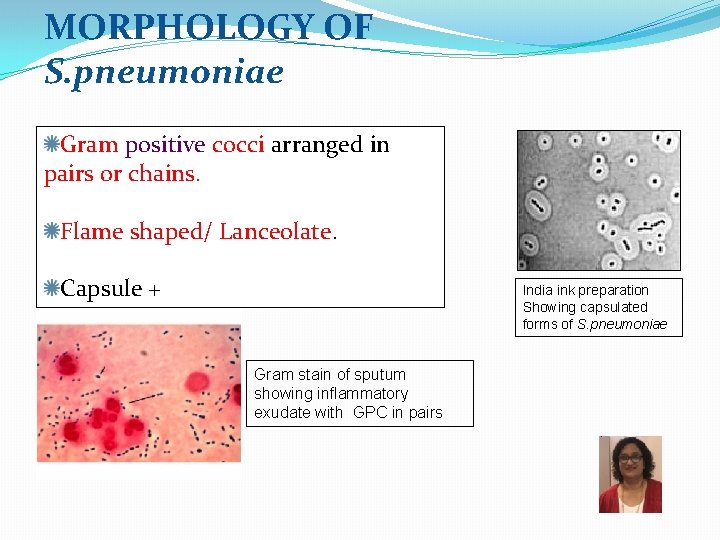

MORPHOLOGY OF S. pneumoniae Gram positive cocci arranged in pairs or chains. Flame shaped/ Lanceolate. Capsule + India ink preparation Showing capsulated forms of S. pneumoniae Gram stain of sputum showing inflammatory exudate with GPC in pairs